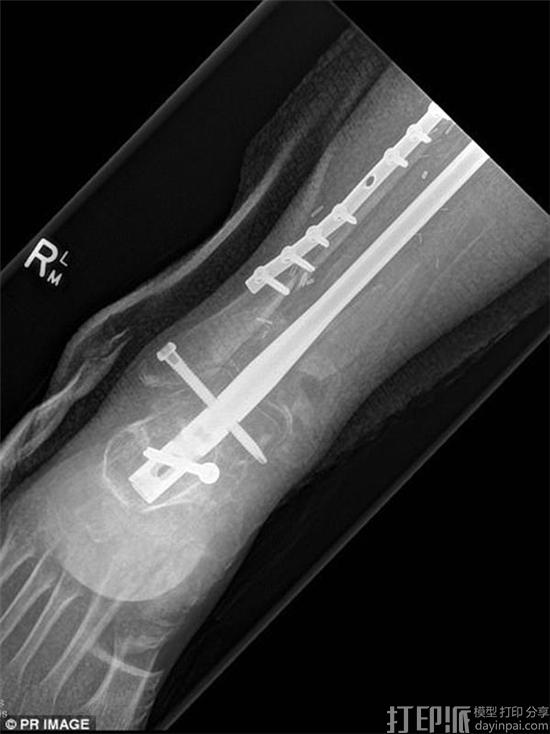

据了解,手术所用的3D打印胫骨支架长36厘米,是由昆士兰科技大学设计,然后在新加坡使用生物降解型聚合物材料制造的。手术之前,医生们用血管和取自Lichter的胫骨组织将其包裹,而手术时,这些组织已经开始生长。所以最终,如果一切顺利,这些组织便会长成全新的胫骨。

值得一提的是,这是全球首例3D打印胫骨支架植入手术,而Lichter也因此成为了世界首个接受此类手术的人。另外在手术之前,医生们就一直用羊进行着活体实验。所以这次,他们才有信心为Lichter实施手术。